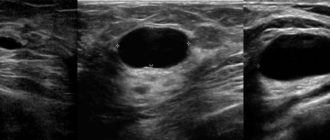

УЗИ картина м/железы. Кисты левой молочной железы

Ультразвуковое исследование при раке молочной железы (часть 2) » УЗИ для женщин » 2018